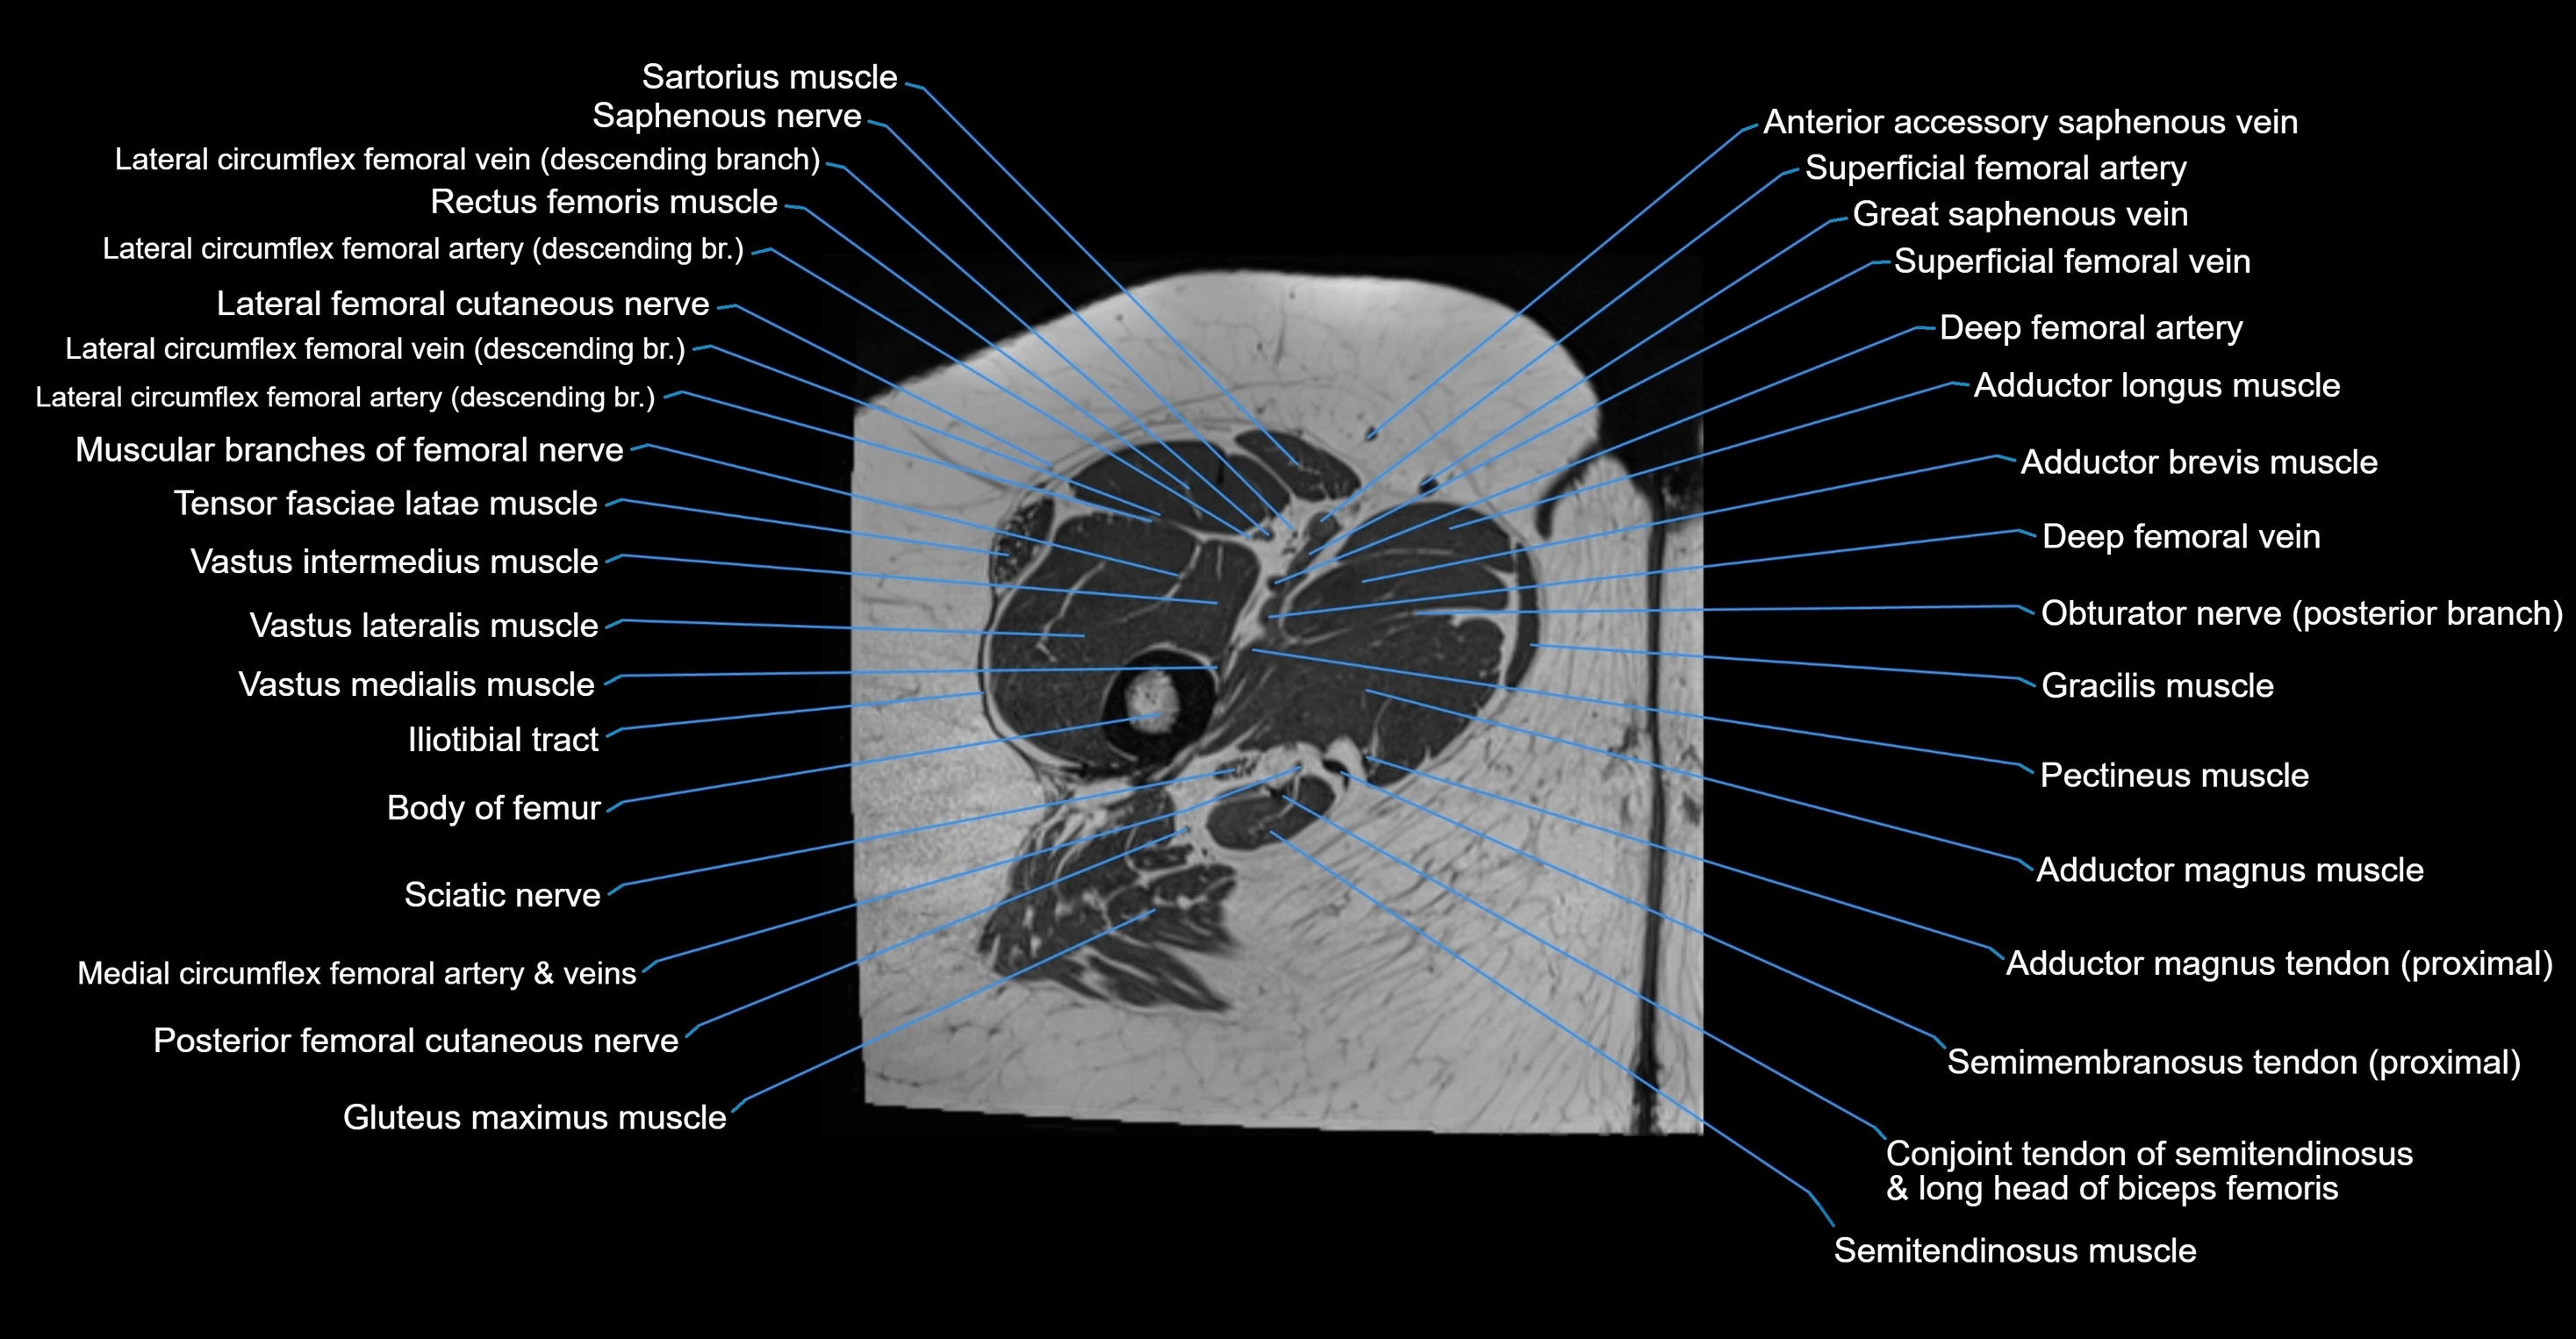

- Adductor brevis muscle

- Adductor longus muscle

- Adductor magnus muscle

- Adductor minimus muscle

- Body of femur

- Deep femoral artery (profunda femoris)

- Deep femoral vein (profunda femoris vein)

- Gluteus maximus muscle

- Gracilis muscle

- Iliotibial tract

- Lateral circumflex femoral artery

- Lateral circumflex femoral veins

- Lateral femoral cutaneous nerve

- Medial circumflex femoral artery

- Medial circumflex femoral vein

- Muscular branches of femoral nerve

- Pectineus muscle

- Posterior femoral cutaneous nerve

- Rectus femoris muscle

- Saphenous nerve

- Sartorius muscle

- Semimembranosus tendon (proximal)

- Superficial femoral artery

- Tensor fasciae latae muscle

- Vastus intermedius muscle

- Vastus lateralis muscle

- Vastus medialis muscle

- great saphenous vein